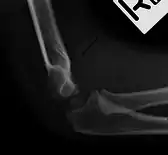

لا توجد قيمة لعلامة الوسادة الدهنية في تقييم كسر مفصلي في المرفق. عادة ما تكون علامة الوسادة الدهنية الأمامية طبيعية، أما العلامة الخلفية التي تظهر في صورة بالأشعة السينية لمفصل المرفق فهي غير طبيعية. في هذه الحالة، فإن المريض سيكون عاجزا عن ثني المفصل ويحتاج تداخلا من قبل طبيب عظام وكسور.[2]

علامة الوسادة الدهنية الأمامية الطبيعية لذراع سليمة